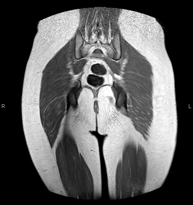

RM de Glutis

RM de GlutisExploració per estudiar la musculatura i dels tendons que s'originen en aquest nivell, com els tendons isquiotibials, lesió sovint en esportistes. La durada aproximada és de 16 minuts. No empra radiació ionitzant.